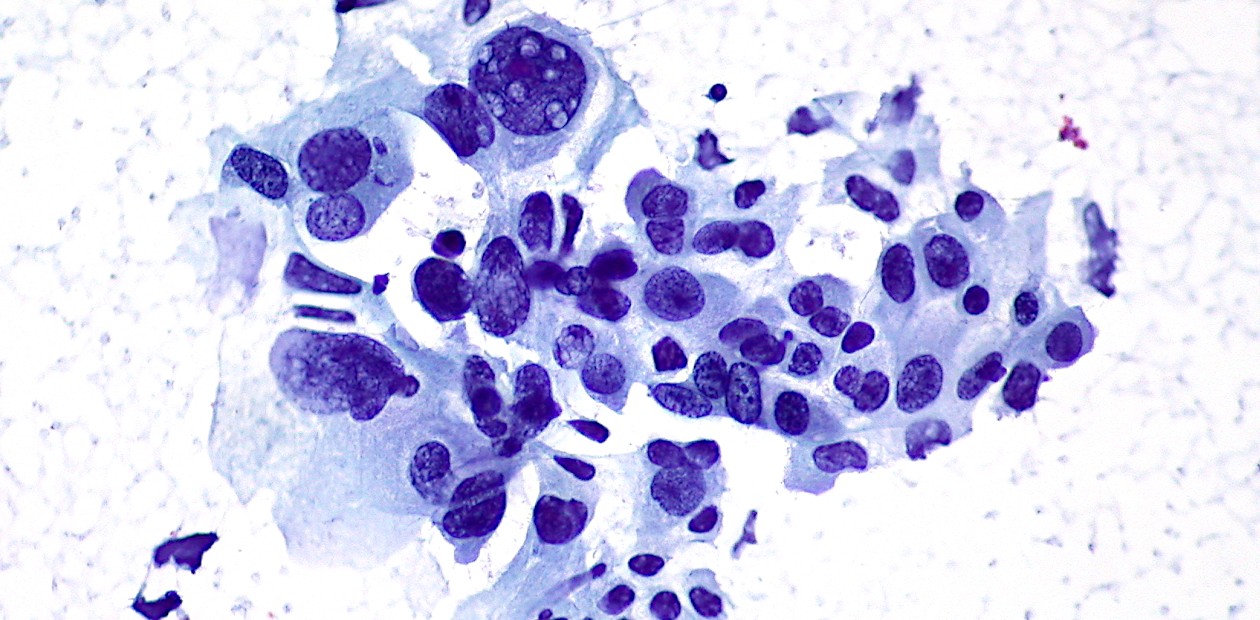

С помощью системы редактирования генома CRISPR/Cas они ввели соответствующие онкогенные мутации в ДНК клеток легких взрослых молодых (4–6 месяцев) и старых (20–21 месяцев) мышей. Пятнадцать недель спустя количество раковых клеток в легких у молодых животных было примерно в три раза больше, чем у старых. Опухоли у молодых также были значительно крупнее, хотя имели схожую гистологию. Все это свидетельствует о более тяжелом течение болезни.

В следующем эксперименте животным предварительно вводили разные генетические мутации, инактивировавшие у них различные гены-супрессоры опухоли, которые препятствуют злокачественной трансформации клеток. В результате у таких мышей частота возникновения опухолей предсказуемо увеличилась, при этом негативный эффект был также выражен сильнее у молодых мышей! Самое большое влияние оказывала на них инактивация гена PTEN, который кодирует фермент, блокирующий неконтролируемое клеточное деление. В этом случае опухолевая нагрузка у молодых мышей была более чем в 2,5 раза выше, чем у пожилых.